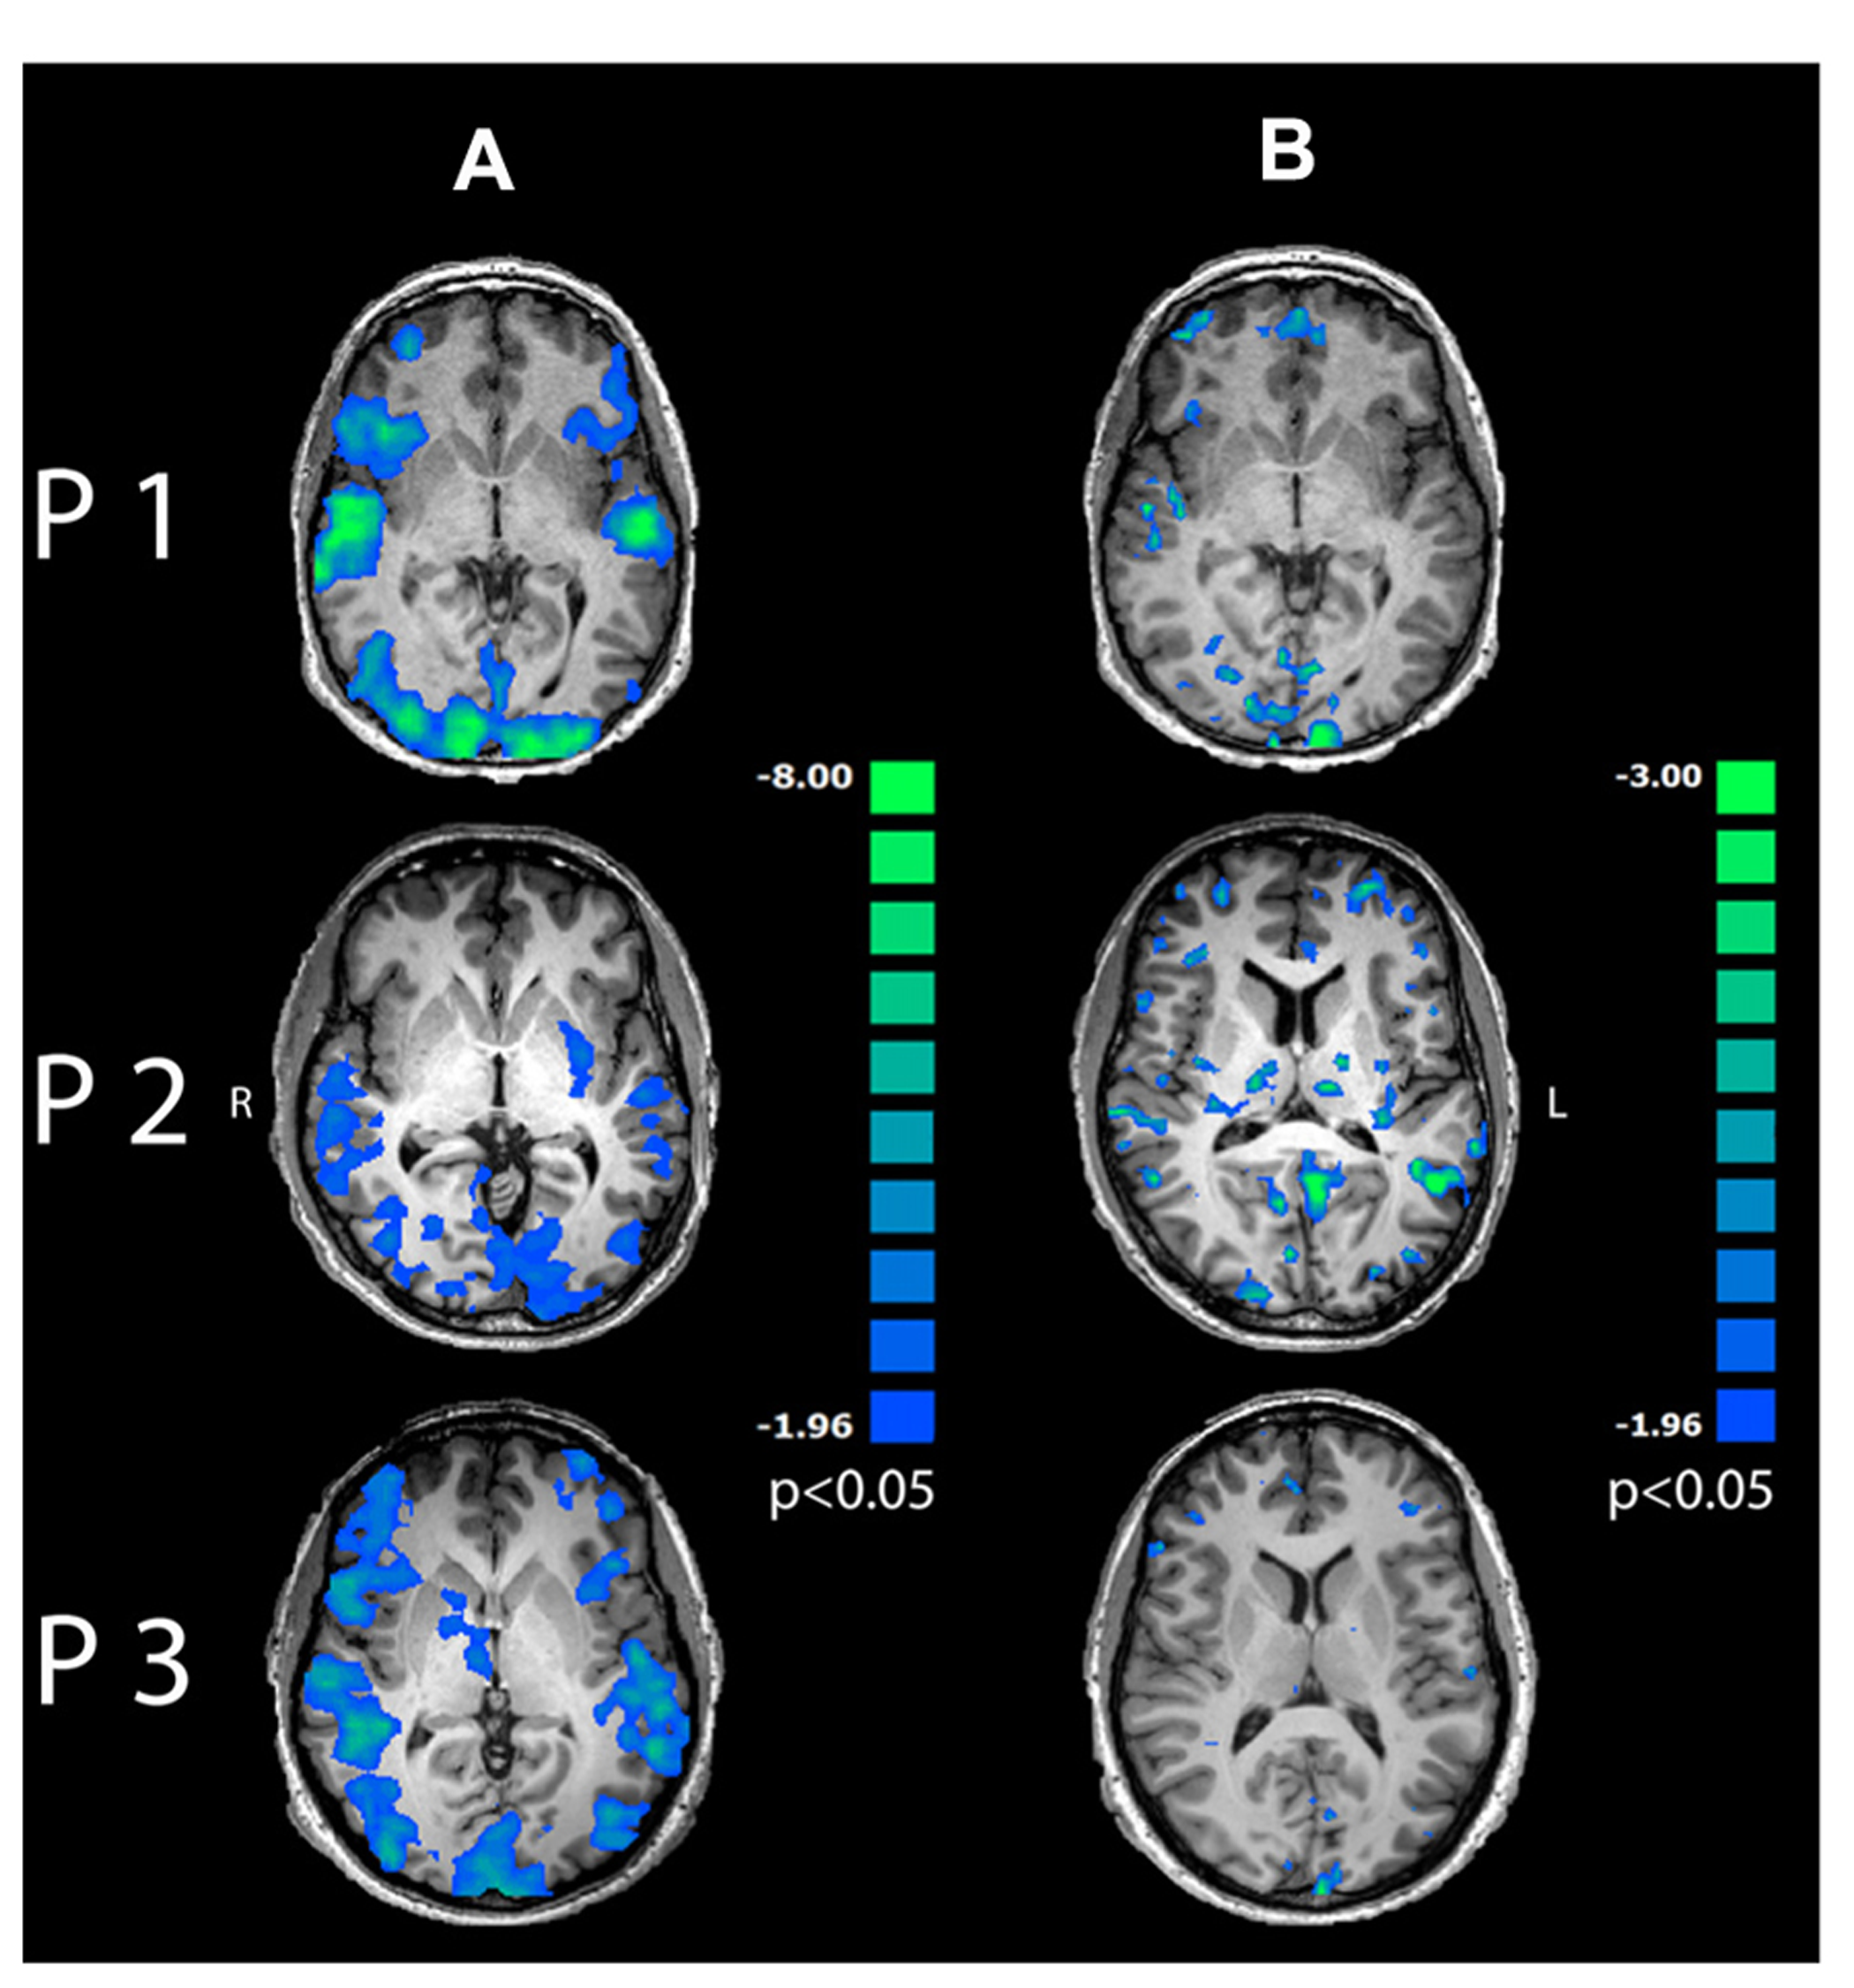

Correlation analysis of induced alpha power in OC

Single-trial variability of induced alpha power to multisensory stimuli in the OC correlated negatively with BOLD response in a wide-spread network encompassing visual and auditory cortices, dorsolateral and prefrontal areas as well as bilateral insula (Figure 6A; p < 0.05, cluster-threshold corrected).

FIGURE 6

Regression maps between induced alpha power during 200–400 ms after stimulus onset and BOLD response for multisensory stimuli. Negative correlations are displayed in cold colors. (A) Induced alpha power over occipital lobe correlated significantly with BOLD response to multisensory emotions in visual, auditory and frontal areas (p < 0.05, cluster-threshold corrected). (B) Induced alpha power in PFC correlated negatively with BOLD response in mediofrontal, dorsolateral and occipital areas (p < 0.05, uncorrected).

Further correlation analysis between time series of induced alpha power during 200–400 ms after presentation onset in the PFC and BOLD response revealed exclusively inverse correlations in mediofrontal, dorsolateral, prefrontal and visual areas (Figure 6B and Table 1, p < 0.05, uncorrected) to emotionally INC stimuli.